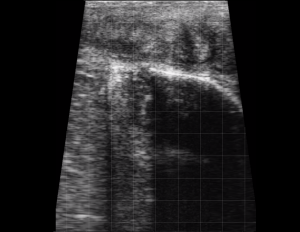

SIMON Ultrasound Database

This ultrasound database is a free resource for students and doctors!

Our collection includes videos of dogs, cats, horses, cows, humans, and many other species!